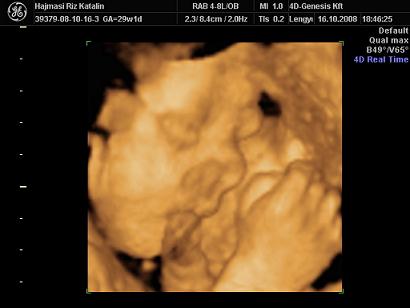

A mi kis álmodozónk